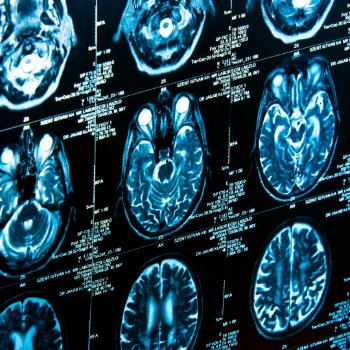

5 Important Things We Learned About Alzheimer’s in 2022

It has been an exciting year in the field of Alzheimer’s and dementia research. As 2022 comes to a close, we look back at progress made, including discoveries into the causes, risk factors and treatment of Alzheimer’s disease and other dementia. Here are five important takeaways: